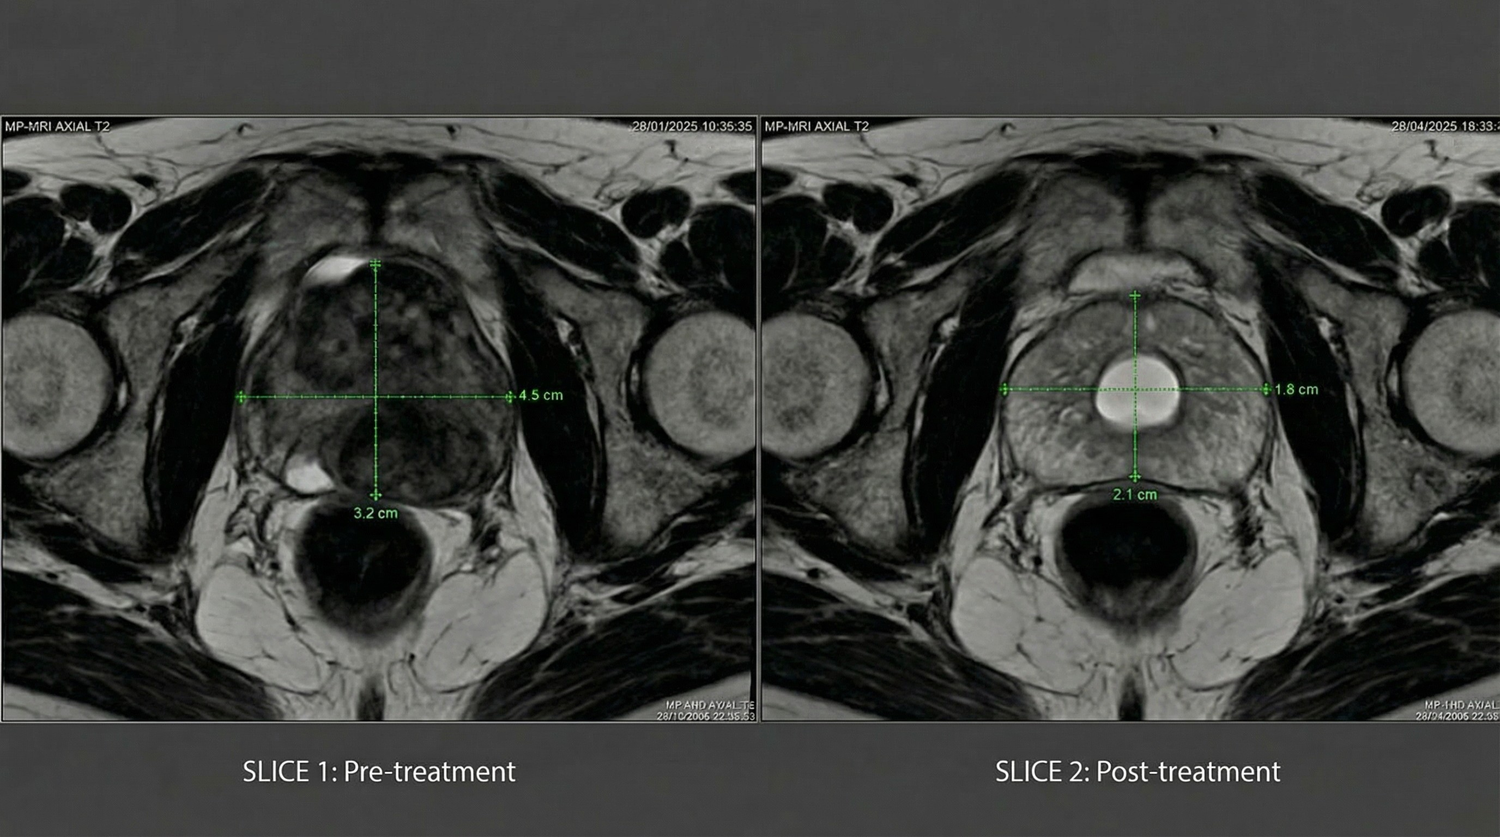

6. Clinically Backed Shockwave Technology

The Tiworld™ uses low-intensity shockwave therapy clinically validated to improve blood flow and stimulate tissue regeneration.

Once limited to clinics, this breakthrough is now available at home, enhancing stamina and erectile function naturally, without drugs or side effects.

Unlike pumps or temporary aids, Tiworld™ delivers lasting results.